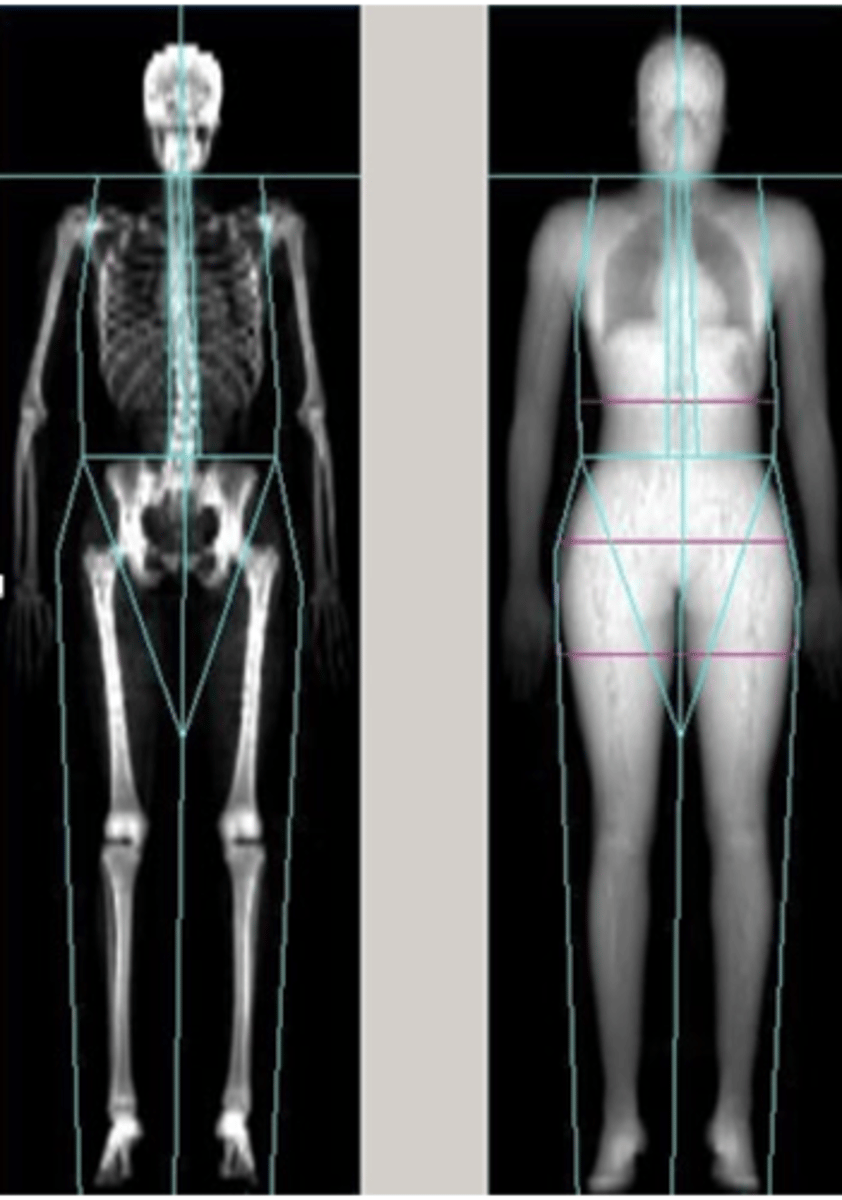

diagnosis and treatment (osteoporosis)

Dual-energy X-ray absorptiometry (DXA or DEXA)

DXA is recommended for:

-- All people 65 years and older

-- Women 60 to 64 years with increased fracture risk

Imaging options:

-- Whole body

-- Lumbar

-- Femur

-- Wrist